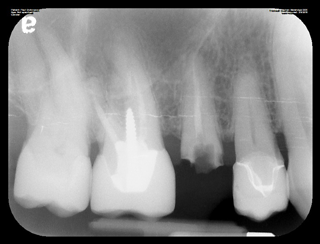

Dental implants are artificial tooth roots made from titanium that are surgically placed into the jawbone. They provide a stable foundation for replacement teeth, such as crowns or bridges, ensuring a natural look and feel. The implants fuse with the jawbone over time, offering a long-term solution for missing teeth.

The dental implants procedure involves several steps. First, a comprehensive dental exam is conducted. Then, the implant is surgically placed into the jawbone. After a healing period, during which the implant fuses with the bone, an abutment is attached to the implant. Finally, a custom-made crown is placed on top of the abutment to restore the tooth’s appearance and function.

Ideal candidates for tooth implants are individuals with good oral health, sufficient jawbone density, and healthy gums. If you have missing teeth and are interested in dental implants, a consultation with our dental team at Beveridge Dental will help determine your eligibility. We will conduct a thorough evaluation to assess your specific needs and provide personalized recommendations.